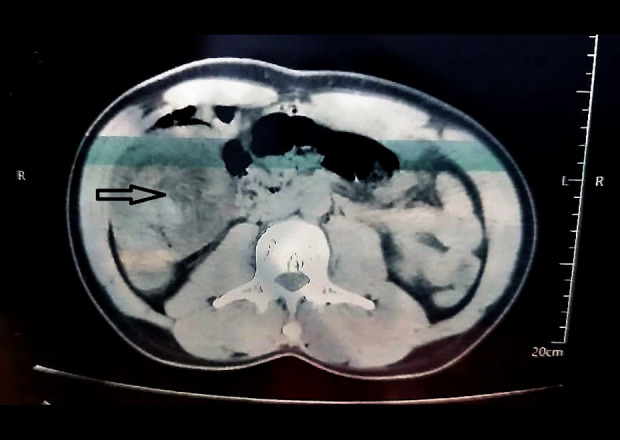

本报告描述了一名36岁男性,因特发性回盲肠肠套叠而出现严重腹痛和小肠梗阻的病例。肠套叠是指肠的一段延伸或折叠到它的远端。这是儿童人群中小肠梗阻的主要区别之一,但在成人中仍然非常罕见。成人肠套叠通常与消化道器质性肿物有关,尤其是肿瘤,它作为牵引点,将近端肠拖入远端肠段。在没有明显潜在肠道病理的成人患者中发现肠套叠是非常罕见的。病例报告:我们报告一例成年患者的回盲肠肠套叠,手术探查和病理检查均未发现潜在的肠道异常。患者,36岁男性,表现为剧烈腹痛,通过计算机断层扫描(CT)诊断为肠套叠。药物治疗失败后进行手术切除和肠吻合术。患者术后一个月出现腹泻和维生素缺乏性神经病变,诊断为短肠综合征,经适当治疗后痊愈。结论:肠套叠虽然在成人患者中很少见,但即使没有潜在的肠道疾病也可能发生。然而,彻底的手术探查和适当的病理分析对于排除其他肠道异常至关重要。临床医生应该意识到可能的并发症,如短肠综合征,如果采用手术方法和大量的肠道被切除。

BACKGROUND This report describes the case of a 36-year-old man presenting with severe abdominal pain and small-bowel obstruction due to idiopathic ileo-cecal intussusception. Intussusception refers to the telescoping or folding of a segment of bowel into the section distal to it. It is one of the main differentials of small-bowel obstruction in the pediatric population, but remains exceedingly rare in adults. Intussusception in adults is generally associated with organic masses of the digestive tract, especially tumors, which act as lead points that drag the proximal bowel into a more distal segment. It is extremely uncommon to find intussusception in an adult patient with no obvious underlying bowel pathology. CASE REPORT We report a case of ileo-cecal intussusception in an adult patient that yielded no underlying bowel anomaly on surgical exploration and pathology. The patient, a 36-year-old man, presented with severe abdominal pain and was diagnosed with intussusception through computed tomography (CT) scanning. Surgical resection and anastomoses of the bowel were subsequently performed when medical therapy failed. The patient experienced diarrhea and vitamin-deficient neuropathy a month after surgery, which was diagnosed as short bowel syndrome, and which resolved with appropriate medical care. CONCLUSIONS Intussusception, while rare in adult patients, is possible even without underlying bowel disease. However, a thorough surgical exploration and proper pathology analysis are essential to confidently exclude other gut anomalies. Clinicians should be aware of possible complications like short bowel syndrome if the surgical approach is used and a significant amount of intestine is resected.